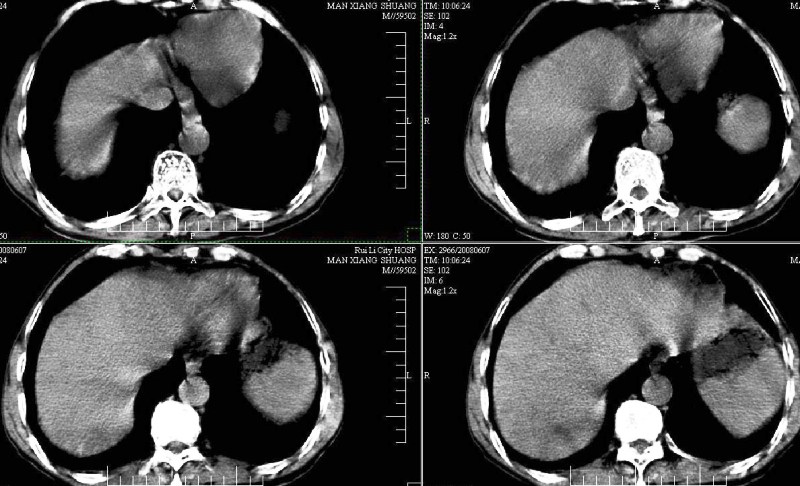

胸部摄片未见异常。临床医生体检发现上腹部饱满。

ct:肝癌腰椎转移。临床医生:肝脏、骨转移,肿瘤来自?前列腺?!

建议强化观察肝内病灶特点,考虑肝癌骨转移。

1、支持肝癌肝内及腰椎转移。

2、肝脏内好象有多个病灶,建议增强检查。